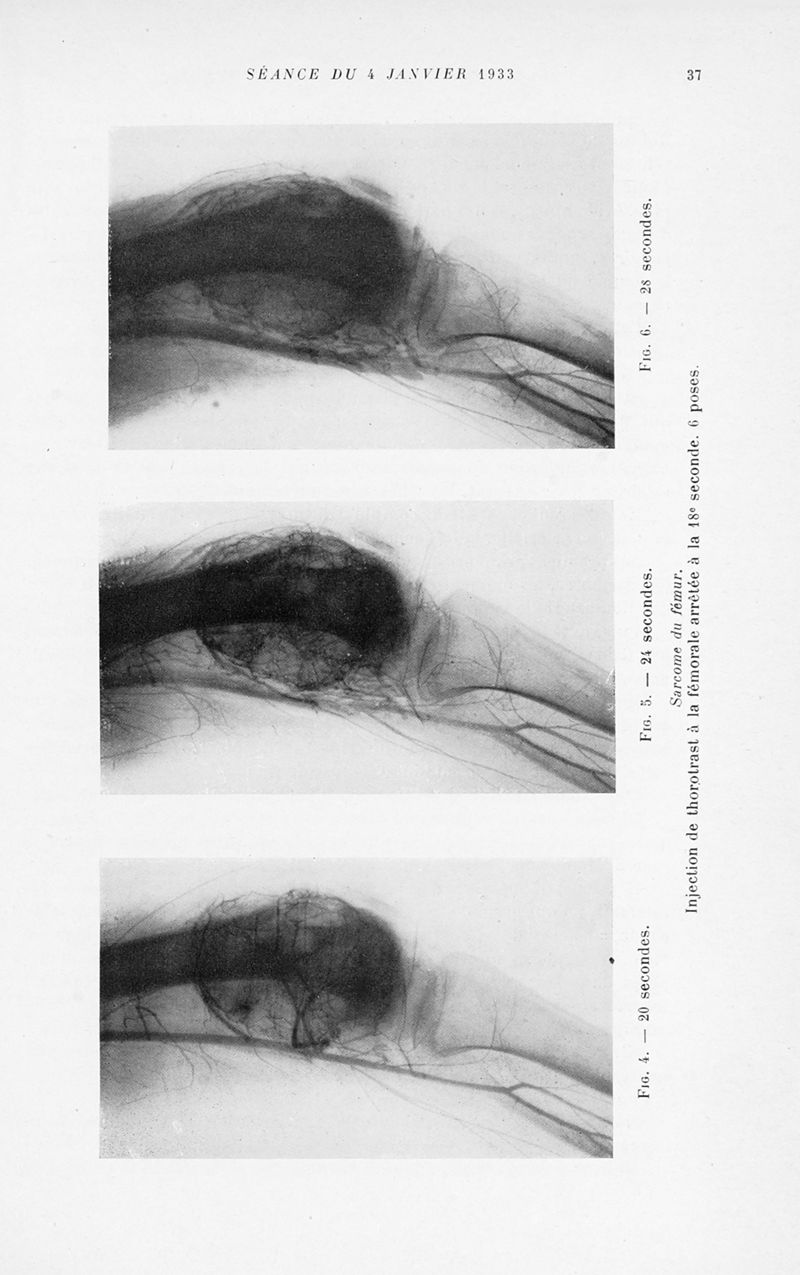

Bulletins et mémoires de la société nationale de chirurgie

Tome LIX, 1933. - Paris : Masson, 1933.